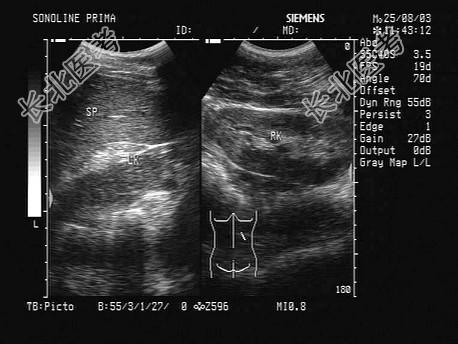

- 单项选择题如图所示,双肾结构清晰, 左肾体积小,该病例最可能诊断是   (   )

A、肾发育不良

B、慢性肾炎

C、慢性肾衰

D、肾萎缩

E、肾脓肿